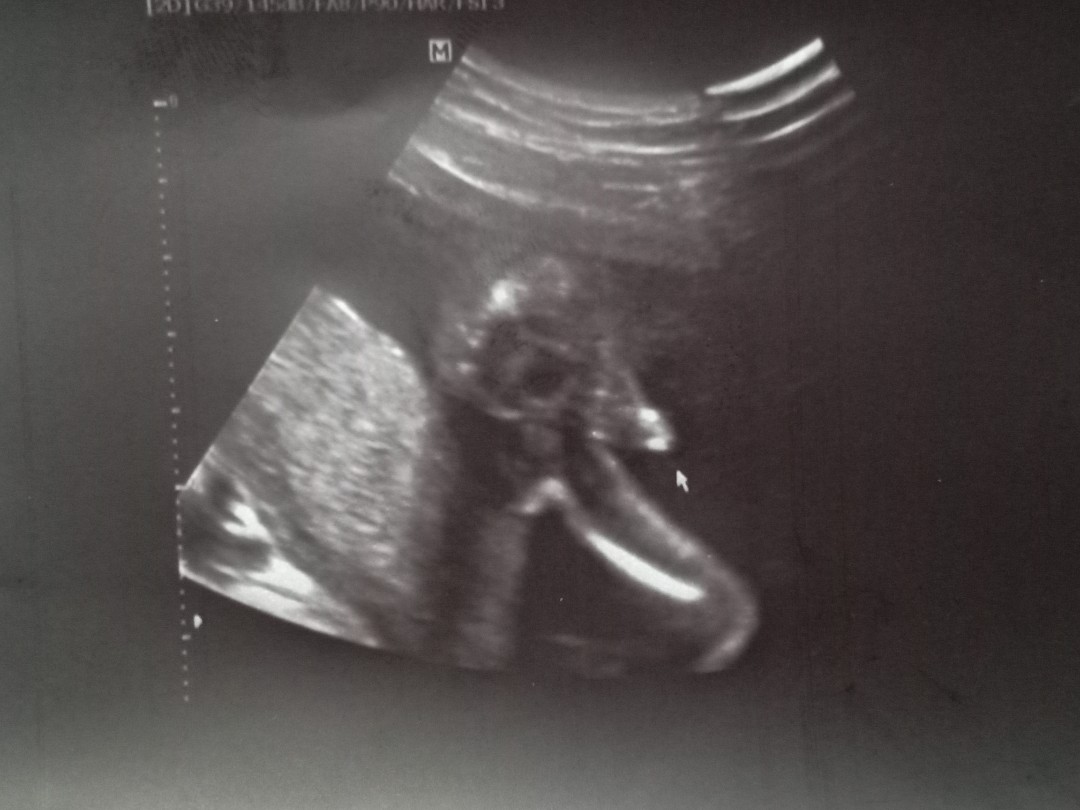

มีแท่งคร่าบบบบบ

หมอบอกผู้ชายค่ะ

จู๋ ..ทั้งคู่ครับ